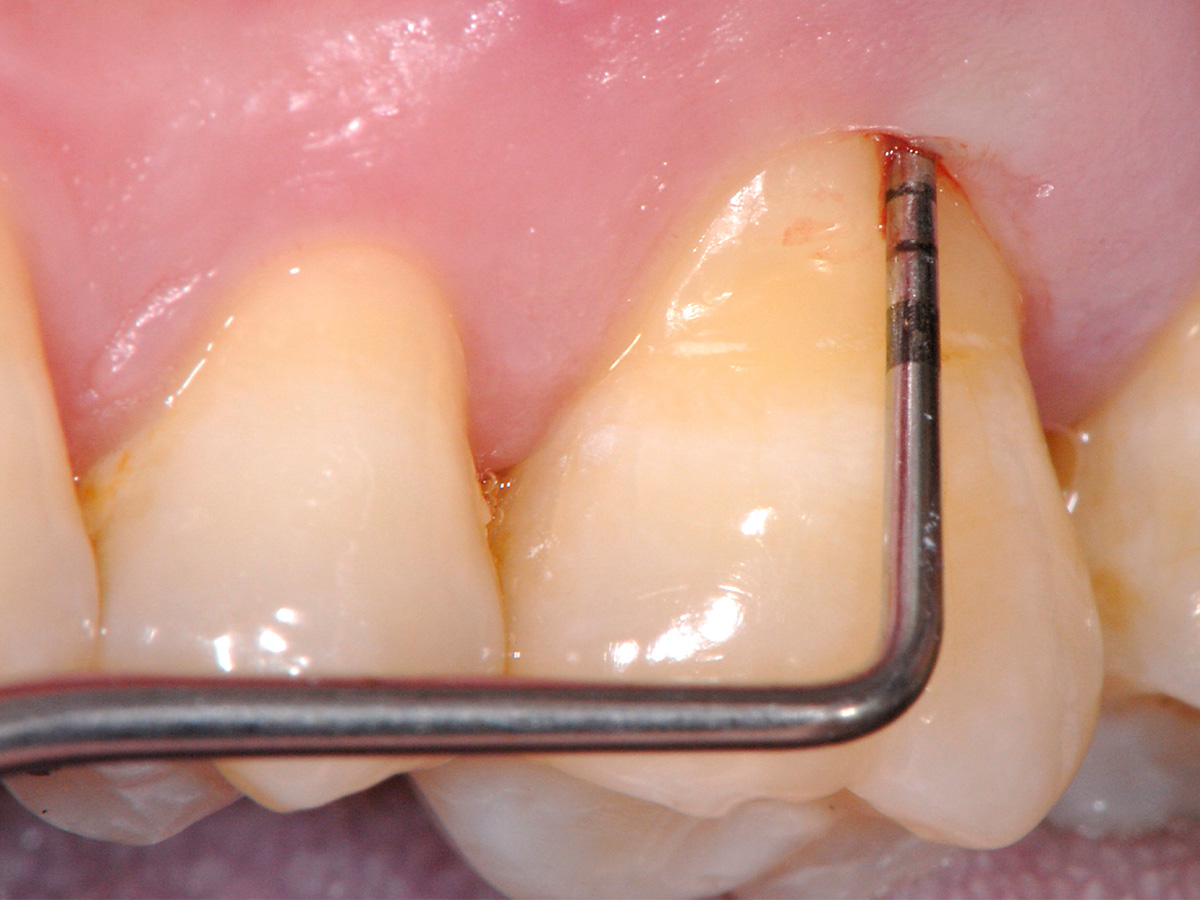

Abbildung 1

Klinische Ausgangssituation: Ausgedehnter parodontaler Furkationsdefekt an Zahn 26 in Kombination mit marginaler Gingivarezession.